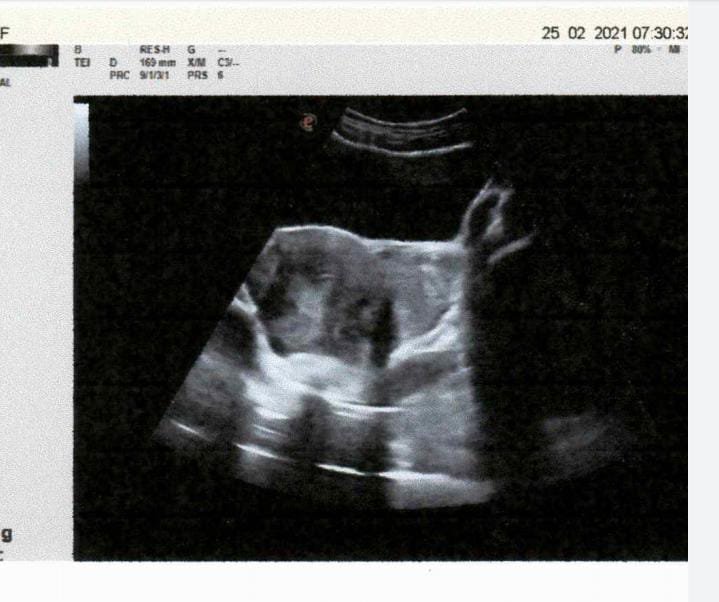

2Mar2021TWO CASES OF TUBAL ECTOPIC PREGNANCY – CASE REPORTS – FEB 2021 Categories CASE STUDY Posted on March 2, 2021May 19, 2025 Author snsblogadminINTRODUCTION: ECTOPIC PREGNANCY OCCURS WHEN A F...